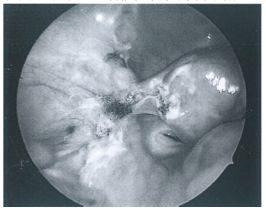

96 下圖為某患者手術完成之腹腔鏡圖,顯示此患者接受何種婦科手術? (A) Right ovarian cystectomy (B) Left ovarian cystectomy (C) Right adnexectomy (D) Left adnexectomy